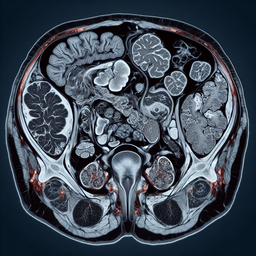

Магнітно-резонансна томографія (МРТ) малого тазу у жінок є неінвазивним методом діагностики, який використовує магнітні поля та радіохвилі для отримання детальних зображень внутрішніх структур тазової області.

- Аномалії матки, яєчників та фаллопієвих труб.

- Пухлини, включно з доброякісними (міоми) та злоякісними (рак яєчників, матки).

- Ендометріоз та інші запальні захворювання.

- Причини незрозумілих болів у тазовій області.